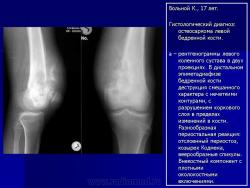

Телеангиэктатическая остеосаркома - редкий (составляет около 4% всех остеосарком) вариант остеосаркомы, характеризующийся наличием кист, заполненных кровью. При рентгенологическом исследовании обычно выявляется полностью литическое поражение без признаков склерозирования, интенсивное вздутие кортикальной пластинки и ее деструкция, часто обнаруживаются периостальная реакция и распространение патологического процесса в мягкие ткани. Гистологическая диагностика телеангиэктатического варианта остеосаркомы может быть относительно несложной при наличии атипичного остеогенеза и высокой степени анаплазии клеточных элементов. Однако довольно часто, особенно у детей и подростков, диагностика вызывает значительные трудности, так как эта остеосаркома, в основном, представлена высокодифференцированным вариантом. Последний отличается тем, что опухолевые клетки определяются только в области выстилки кист и полостей опухоли, злокачественные клетки характеризуются низкой степенью анаплазии, опухолевый остеоид обнаруживается лишь при целенаправленном исследовании серийных срезов, встречаются участки ткани, в которых клеточные элементы и остеоид не имеют признаков атипизма и микроскопическая картина полностью соответствует аневризмальной кисте кости, в связи с чем не исключена диагностическая ошибка при исследовании небольшого количества материала, особенно биопсийного. Относительно медленное развитие опухоли, обычно чисто литическое поражение кости, сходство рентгенологической картины с аневризмальной кистой или гигантоклеточной опухолью кости также способствуют постановке неверного диагноза.